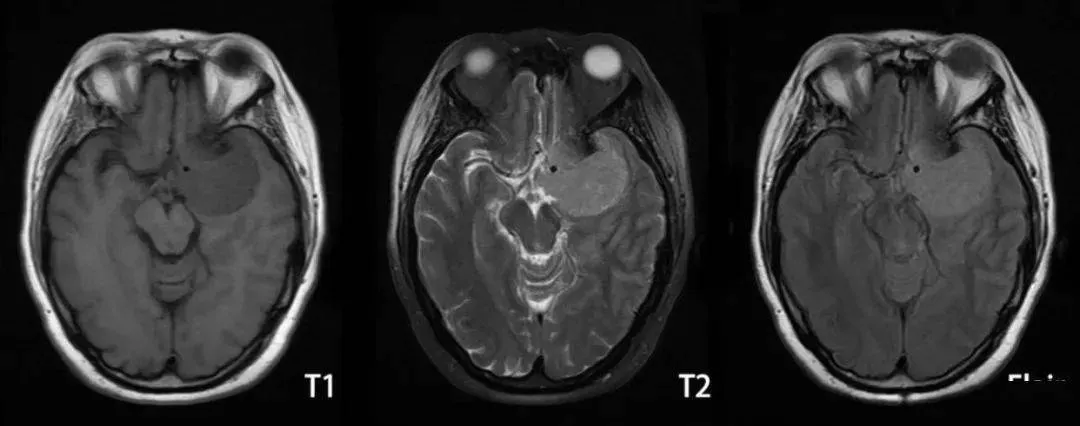

2、磁共振(MRI):近年来,随着患者对CT诊断疾病的同时带来的辐射及对微小病变发现的局限,磁共振检查成为越来越多患者的选择。MRI扫描检查可以任意角度成像,从而对肿瘤的形态进行异常的显示,更具有直观性。

MRI定位、定性颅内肿瘤是从以下几个方面着手的:肿瘤的部位;肿瘤信号特点;肿瘤的边缘;肿瘤的血供;肿瘤的增强情况;周围水肿情况等。MRI因其特殊的成像原理,对诊断肿瘤的性质更有优势,近年来随着磁共振检查方法的不断改进,比如:动态增强诊断垂体微腺瘤、波普检测肿瘤细胞的代谢状况等等方法使用为脑肿瘤患者的后续治疗提供一定的指导。

图片脑膜瘤MRI影像